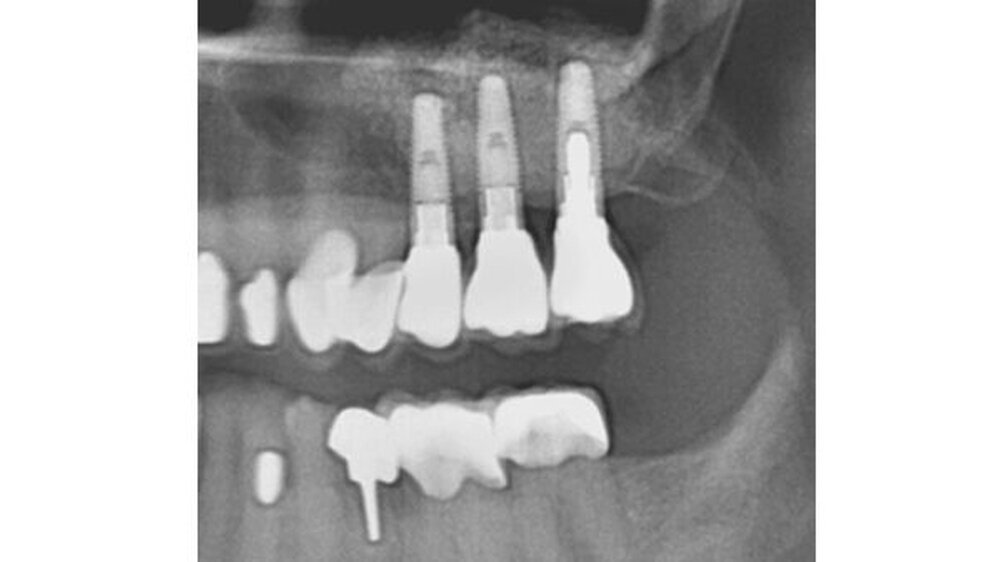

Ayna dokumentierte die chirurgisch aufwendige Behandlung eines Duisburger Patienten. Dabei handelte es sich um den Knochenaufbau in der Kieferhöhle, den Sinuslift. 14 Jahre nach dem Einsatz des anorganischen Rinderknochen-Materials (ABBM) führte Ayna eine histologische und eine mikroradiografische Untersuchung des eingelagerten Materials durch.

Ergebnis: Das Material wurde auch nach diesem langen Zeitraum nicht vom Körper aufgelöst. Vielmehr kam es zu einer erfolgreichen Knochenneubildung. Aynas Untersuchung weist in dem aufgebauten Knochenbereich einen Eigenknochenanteil von mindestens 14 Prozent nach. Die histologischen Untersuchungen lassen darauf schließen, dass der Sinuslift in den zentralen Bereichen aus vitalem Knochen besteht.